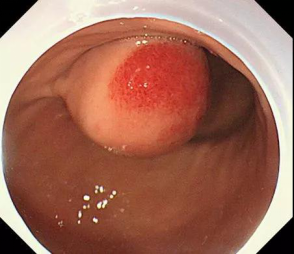

近日,市中医院消化内科在胃镜下通过微创技术,为利州区宝轮镇新街4组余××成功挖出了直径达5公分如土豆大小的“胃间质瘤”,术后恢复良好,痊愈出院。

胃间质瘤是医学上的新词,是21世纪才正式命名和普遍使用的医学新名词。这种病变在胃镜下的形态学表现和我们常说的胃癌、胃淋巴瘤、胃息肉能直接区分开,因为它生长源于固有肌层,像土豆生长一样,可以通过超声内镜检查和CT检查确诊。